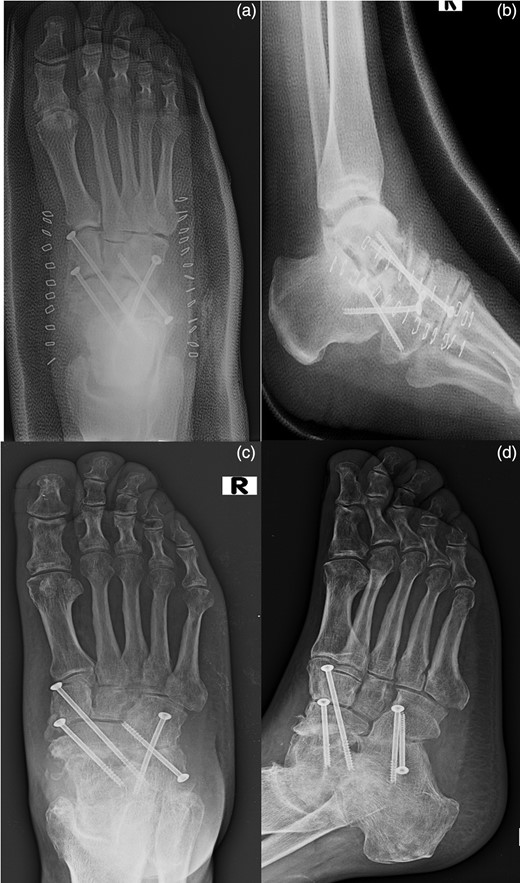

The fixation of the calcaneocuboid joint was carried out using two 4.0-mm cannulated screws. The screws were brought from proximal to distal, starting in the anterior process area and brought obliquely across into the cuboid (Fig. 4).

The placement of an autologous graft into the talonavicular joint harvested from the omolateral iliac crest (a). The fixation of the calcaneocuboid joint was carried out using two 4.0-mm cannulated screws (b) and the talonavicular joint was fused in situ using two 4.0-mm cannulated screws across the talonavicular joint (c).

The foot was put in a cast and kept non-weight bearing for 10 weeks, with range-of-movement exercises of the knee and hip allowed. The patient was reevaluated during a clinical and radiographic follow-up at 1, 3, 6 months after surgery. The arthrodesis was consolidated in ∼3 months. There were no infectious problems and the patient has resumed normal work activities [4].

At the sixth month follow-up, the patient had returned to work and remained pain free while walking, with good fusion of both joints (Fig. 5).

AP (a) and lateral (b) radiographs of the foot in the cast after the surgical time. AP (c) and lateral (d) radiographs of the foot at the sixth month follow-up.